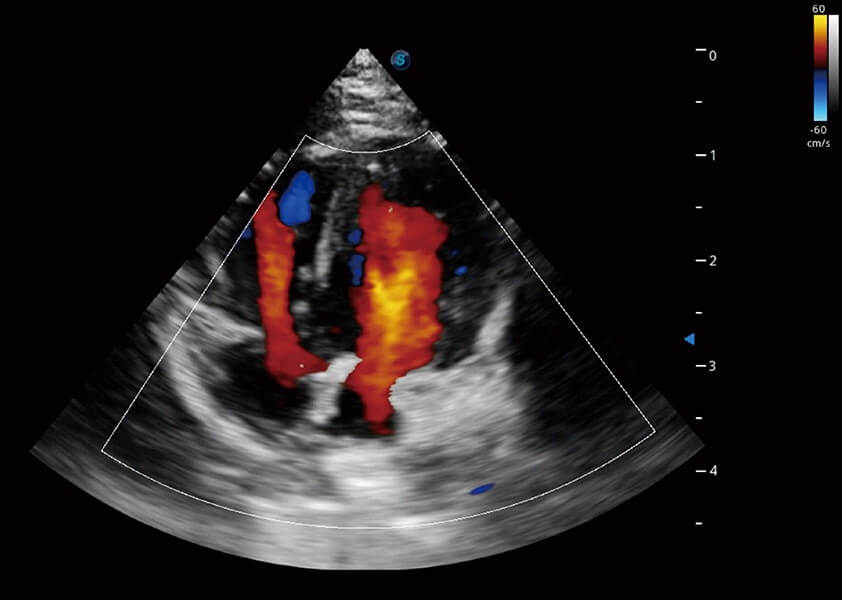

心脏解决方案

ProPet 60 配备了丰富的心脏探头群、先进的成像技术和专业的心脏测量工具,可帮助动物医生为不同体型和生理结构的动物提供心脏和心肌功能的全面评估。

• TDI 组织多普勒成像

实时用颜色表示心肌组织运动,观察和定量组织的运动情况,对快速检测与评估心肌的灌注和活性、电传导及心肌收缩和舒张功能等均能提供重要的诊断信息。

• MQA 心肌定量分析

通过心肌识别技术与二维斑点追踪技术相结合,对心脏的超声图像进行量化分析。计算心肌17个节段的应变、应变率、速度、位移等,并通过牛眼图的形式进行呈现。

• AMM 解剖M型

通过360度任意调节3条M型取样线,在同一心动周期上观察心脏不同位置的运动曲线,得到准确的心功能测量数据,有效评估心肌运动及左心室功能。

• Stress Echo 负荷超声心动图

具备多种协议可选,同时支持17阶段划分法和专业的SE报告。

(犬)四腔心血流

(犬)心脏组织多普勒

(犬)乳头肌短轴

(猫)二尖瓣M型